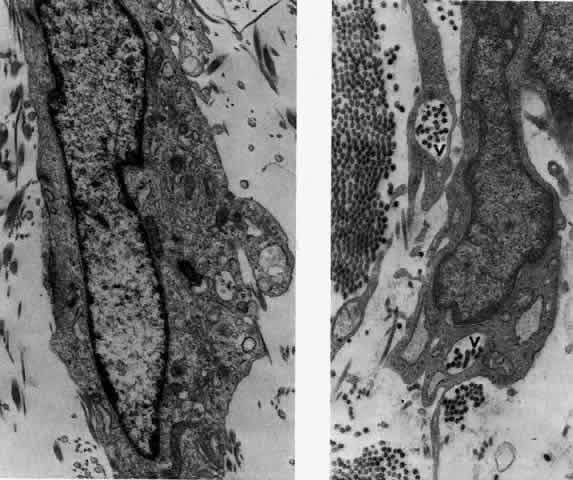

What is clinically represented solely by inflammation and edema is histopathologically a granulomatous lesion of the sclera, the center of which consists largely of plasma cells, lymphocytes, and mast cells (Figs. 21 through 23). Foster and colleagues have identified the cellular subsets and glycoproteins in both necrotizing and non-necrotizing scleritis.22 This shows an active T-cell inflammatory response with a high CD4/CD8 ratio and increased HLA/DR and CD14, indicating a macrophage-induced response that would lead to granuloma formation. Remote from the granuloma, the fibrocytes of the sclera become activated, the proteoglycan adjacent to them becomes altered, and the collagen fibrils of the sclera become unraveled (Figs. 23 and 24). These changes appear to take place prior to the invasion of the stroma by cells of the granuloma.20 The vessels in and around the necrotic area show medial necrosis and perivascular cuffing with lymphocytes, and endothelial swelling with microvascular occlusion. Ninety-six percent of the specimens examined by Foster and associates show a microangiopathy characterized by a neutrophil infiltrate in and around the vessel wall.22–23 This is most obvious at the center of the lesion where there may be occlusion of the vessel, thrombosis, or even aneurysm formation (Fig. 25). From these pathologic investigations, clinical observations, animal experiments, and the results of fluorescein angiography, it would appear that the scleral inflammation is initiated either by trauma (be it accidental or surgical)23–25 or by bacterial or viral infection. If circulating immune complexes are present because of the poor blood flow, they become precipitated in and around the vessel walls in the area of inflammation. In other patients, a persistence of tissue damage will lead to autoimmunization. Damage to the endothelial cells of the microvasculature leads to changes within the vessels detectable on angiography and to catabolic changes in the surrounding tissues. These changes, in turn, allow the granulomatous response that is seen in histopathologic sections, the first detectable change being in the scleral fibrocytes and the proteoglycan and collagen remote from the site of cellular infiltration.

Fig. 22. Electron micrograph of an area of active scleritis showing the plasma cell infiltrate suggestive of an immune response. Note aggregated plasma cells, with the characteristic whorled rough endoplasmic reticulum, in the process of degeneration, releasing organelles and nuclear debris into the extracellular matrix. (Uranyl acetate and lead citrate. X3000) (Courtesy of Dr. R. Tripathi)

Fig. 23. Electron micrographs of scleral stroma at the periphery of an area of ulceration in a patient with necrotizing scleritis. The left shows an active fibroblastic cell, and the right shows collagen fibrils within intracellular vacuoles (V) in the fibroblastic cell. (Left X15,375; right X15,375) (Watson PG, Young RD: Changes at the periphery of a lesion necrotizing scleritis: Anterior segment fluorescein angiography correlated with electron microscopy. Br J Ophthalmol 68:781–789, 1984)